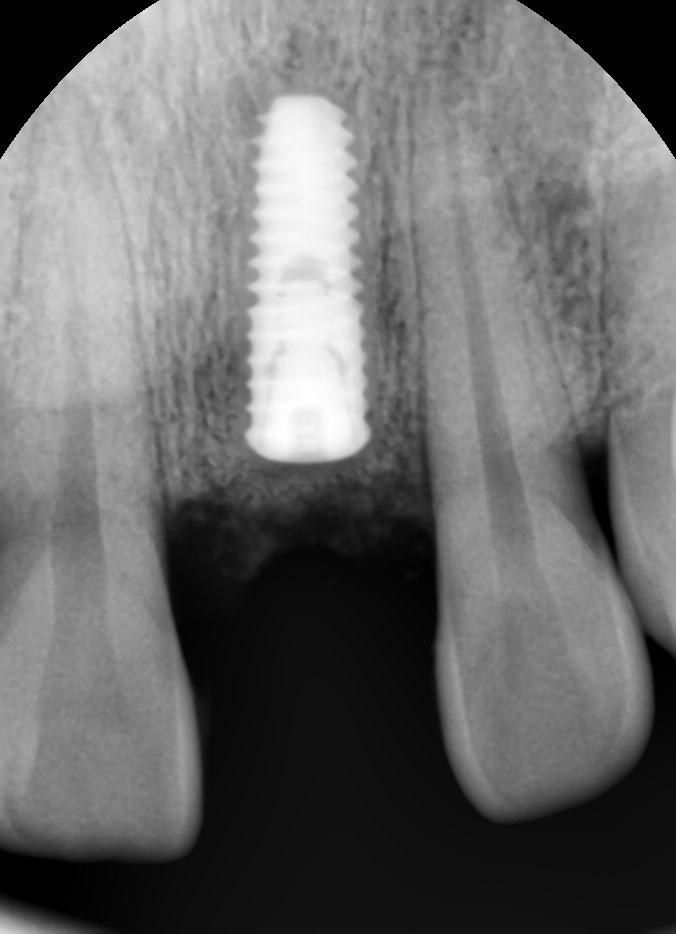

발치 당일 임플란트를 식립 후 엑스레이 사진입니다.